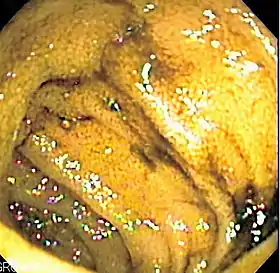

![]() Endoscopic image of normal small bowel | |

Double-balloon enteroscopy, also known as push-and-pull enteroscopy, is an endoscopic technique for visualization of the small bowel. It was developed by Hironori Yamamoto in 2001.[1] It is novel in the field of diagnostic gastroenterology as it is the first endoscopic technique that allows for the entire gastrointestinal tract to be visualized in real time.[2]